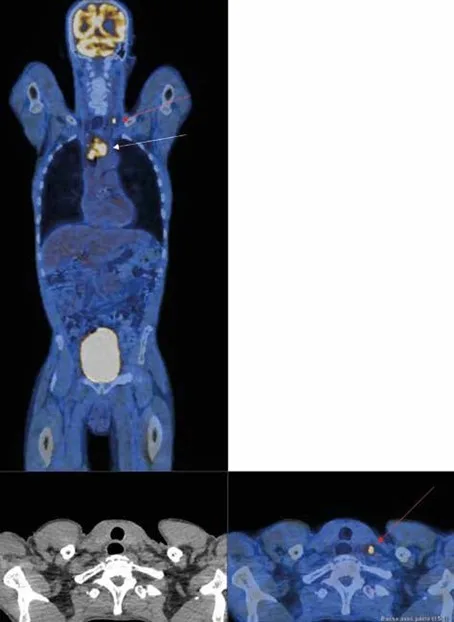

Évaluation de la réponse au traitement du cancer rectal (Figure 1)

Dans le cancer rectal, la TEP au FDG présente de très bonnes performances, notamment de spécificité pour l’évaluation de l’atteinte ganglionnaire des aires iliaques internes, externes et obturatrices, atteintes fréquentes dans les lésions du bas rectum ou les lésions T3-T4 [14].

Les méta-analyses de Maffione et al. et Rymer et al. [15,16] ont retrouvé de bonnes performances de la TEP FDG pour prédire la réponse histologique complète après radio-chimiothérapie néoadjuvante, permettant d’identifier les bons répondeurs et conduisant certaines équipes à proposer à des patients en réponse métabolique complète, une stratégie attentiste afin d’éviter une chirurgie radicale [17]. Une étude souligne l’intérêt de la réalisation précoce de la TEP FDG pour l’évaluation de la réponse [18].

La TEP au FDG présente de bonnes valeurs de sensibilité et de spécificité pour évaluer l’efficacité de la radio-chimiothérapie dans le cancer du rectum et identifier les patients qui présentent une réponse complète.

La TEP au FDG peut être proposée à la fin du traitement de radio-chimiothérapie du cancer du rectum pour évaluer la réponse au traitement.

Figure 1 : TEP préthérapeutique chez une patiente présentant un cancer du rectum :

Figure 1a : Lésion hypermétabolique rectale très intense (Standardized Uptake Value : SUV max=9.5), flèche rouge.

Figure 1b : Réponse métabolique complète sur la TEP de fin de traitement de radiochimiothérapie, flèche blanche.